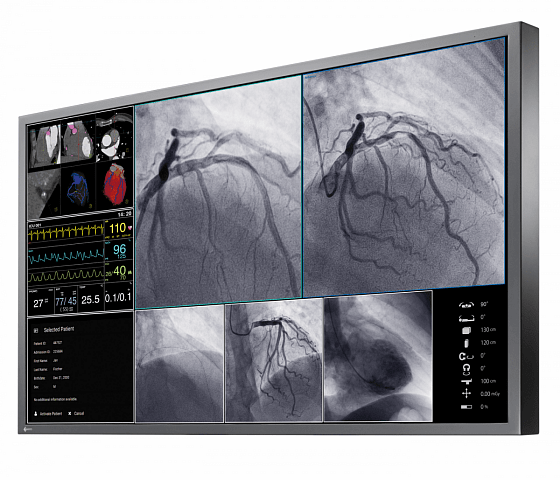

Der 55" Breitbild-Monitor mit 4K UHD Auflösung ist ideal für die Anzeige medizinischer Bilder in der Angiographie, Kardiologie oder Endoskopie geeignet und kann sowohl an der Wand als auch an eine Deckenhalterung montiert werden. Das Sicherheitskonzept und die langlebige Hintergrundbeleuchtung sind ideal für einen langfristigen, stabilen und verlässlichen Einsatz.

- Großer Blickwinkel durch IPS LCD Technologie.

- Optimale Anzeige von DICOM Bildern durch Graustufenabgleich nach DICOM Part 14 Standard ab Werk.

- Einheitliche Helligkeitsverteilung über den gesamten Schirm.